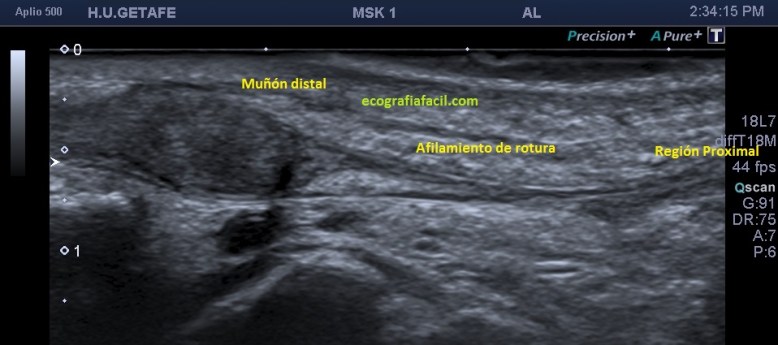

En este recorrido encontré un muñón, que se observa perfectamente en longitudinal, y que correspondía con el extensor largo del pulgar a la altura de su recorrido.

Corte en eje largo correspondiente a la imagen 6, donde se ve claramente lo que pasa y es definitivo para el diagnóstico final.

Esta imagen final demuestra muy claramente lo que ha pasado y como ha quedado la zona en cuestión. El tendón retraído parece continuarse hacia proximal, filiforme, hasta que llega a otro ensanchamiento hipoecogénico, en relación con el muñón proximal.